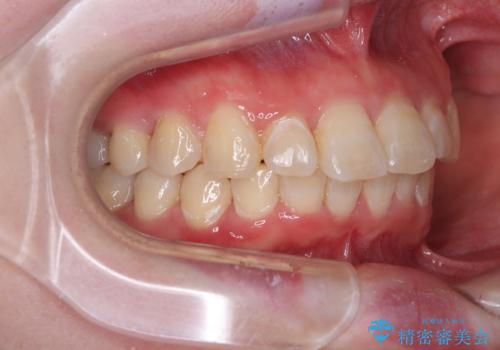

- デコボコの歯列が気になるとことで来院された患者様です。

歯列不正としては軽度であったため、インビザラインでもワイヤー装置でも対応可能でしたが、ご本人の希望によりインビザラインによる矯正治療を行うこととしました。

マウスピース矯正は、自己管理が非常に重要と事前にお伝えしておりましたが、毎日のマウスピース装着が遵守できず、ワイヤー装置での矯正治療へ変更することとなりました。

インビザラインからワイヤー装置へ変更すると、費用が追加となるため、ワイヤー装置は目立つものの費用を抑えることのできるメタルブラケットを使用しました。